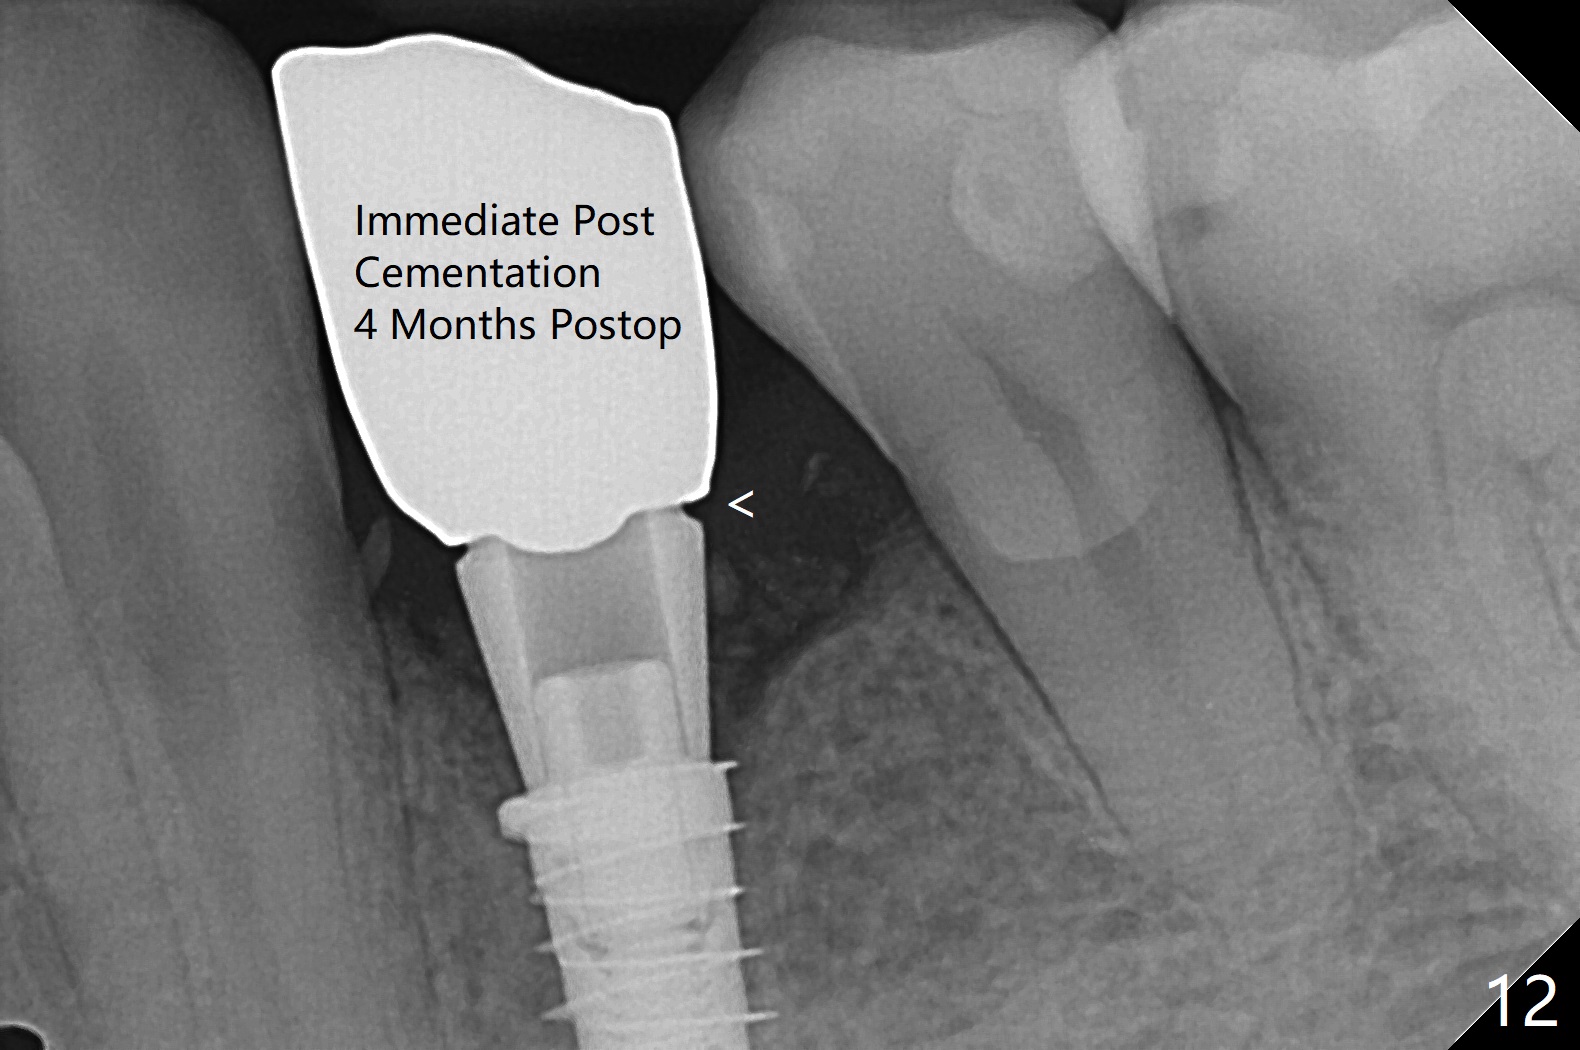

Three months post guide fabrication (coronavirus outbreak), the patient with loose post/crown returns for #21 extraction and immediate implant with guide (Fig.1 (*: post space)). In fact the root stump is flattened with diamond bur and 9 mm bone trimmer with guide before point drill. When the osteotomy finishes with 3.5x13 mm drill (under drilling with 10.5 mm offset), it has deviated buccal (Fig.2, 3,4); the outline of the bone trimmer mark is labeled by arrowheads in Fig.2. It appears that the center of the bone trimmer is dictated by that of the post space, as compared to Fig.1 *). When the root is removed except buccal shield (assuming that the deviation was due to the uneven surface of the root stump), the osteotomy is redone with guide, but remains buccal. Finally with buccal shield removal, a new lingual osteotomy is created free hand for a 4.5x11 mm implant (Fig.5) with 2-3 mm buccal gap for bone graft (Fig.6 * (literally)). In brief, bone trimmer also deviates according to resistance, basically irrelevant to the guide sleeve. The immediate provisional is intentionally removed 5 days postop to check whether a piece of gauze is retained in the socket as a gingival retraction cord for temporary crown fabrication; the buccal gap is kept with bone graft (Fig.7 *). No foreign body is in place. The margin of the abutment seems quite subgingival (Fig.8 *), but re-trimmed and polished provisional looks harmonious with the surrounding gingiva and the opposing dentition (Fig.9,10). The patient returns for prophy 2 months postop; the immediate provisional is removed for trimming and polishing. The bone graft seems to be integrated into a part of the gingiva (Fig.11 >). The abutment cuff appears to be too short.